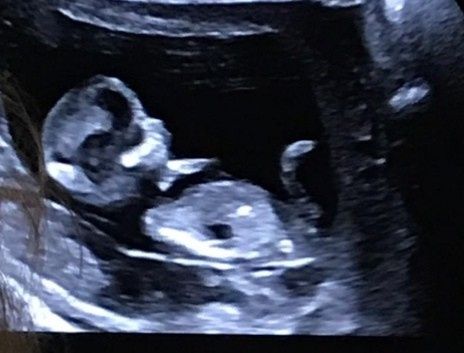

Ecco il fagiolino/a di mia cogantaa ancora non si vede cos'è.. Perché si muoveva tanto..e siamo tutti curiosi..

E chi di voi riesce a capirlo? Baciiiii

Più che giocare con ramzi Io direi che puoi guardarlo con la nub theory perché mi sembra grande... Ha più di 9 settimane? Non sono completamente sicura perché non lo so usare Però a me sembra maschio.....

Eh allora sì giocare con Ramzi è impossibile troppo grande e quindi per forza la nub....

È 12 settimana❤️